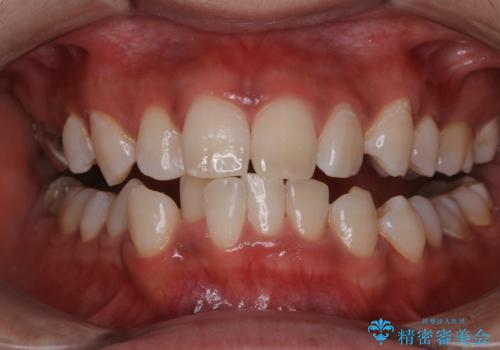

歯列矯正中にPMTC